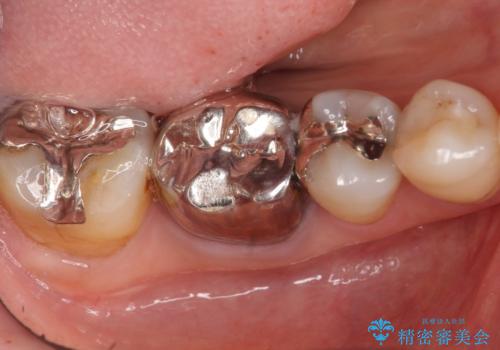

痛みが出るのが怖い・外科手術は避けたいとのご希望でブリッジをご希望されました。

ブリッジの自然な見た目と咬み心地にご満足頂けました。

メタルボンドクラウン(外側はセラミック、内側はメタル)では舌側の歯頚部がメタルの場合が多いのですが、すべてセラミックで覆うフルベイク仕上げでオーダーし、審美性を追求しました。

クラウンの種類:メタルボンドクラウン エコノミー フルベイク